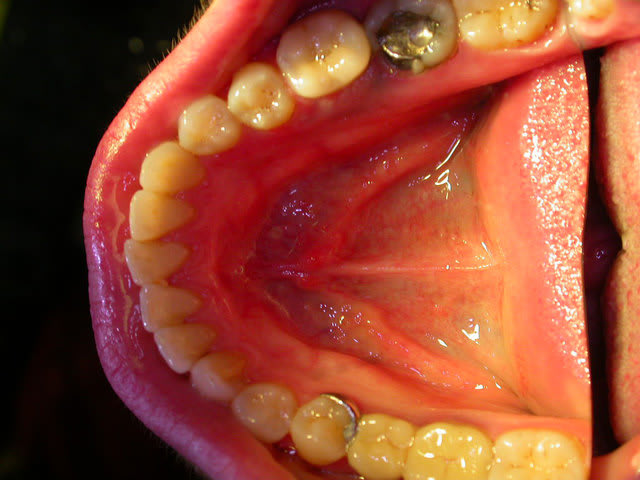

examen buccal .........voir les photos ........après ........ca vient

Bon controle de plaque, pas de tartre ni de colorations, inflammation en palatin seulement...